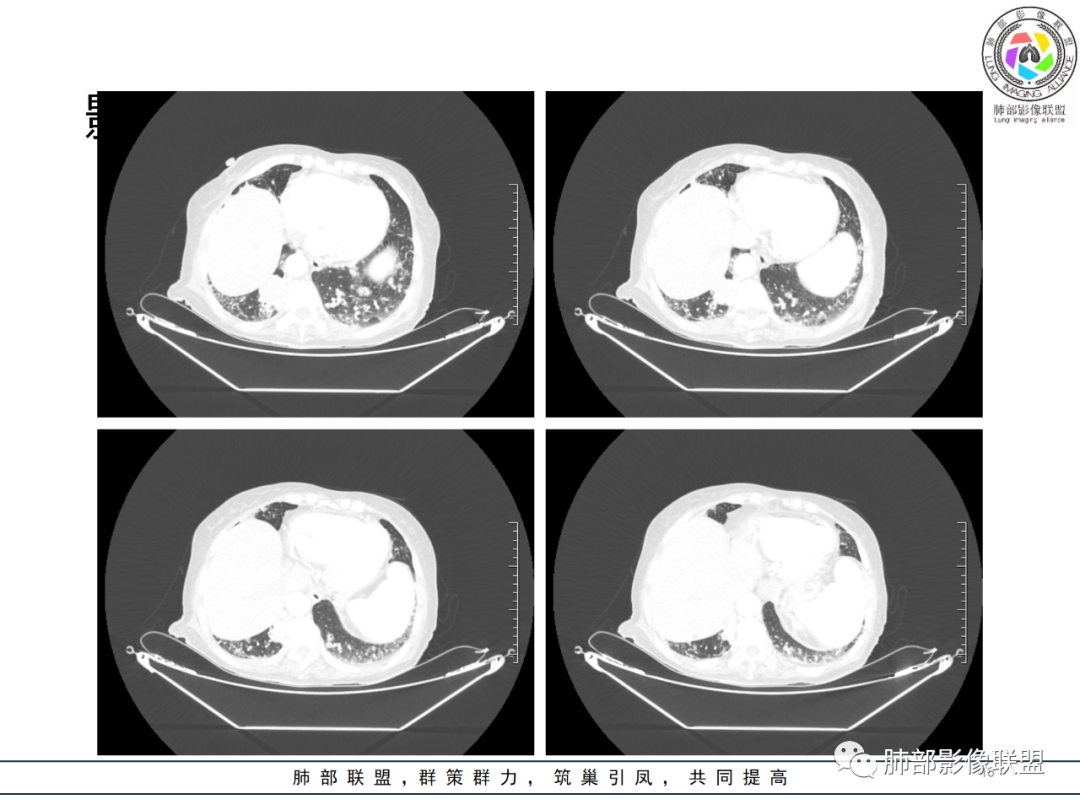

影像资料

老年女性 3个月前发热,双肺支气管血管束增粗改变。3个月后再次发热,影像见双肺广泛支气管血管束明显增粗,较前进展,并延续进入纵隔,另外增强见双肾周增多软组织密度,左肾明显且肾门处形成肿块样改变。综合考虑肿瘤性病变可能性大,1.小圆细胞肿瘤类病变,淋巴瘤?2 全身组织细胞类病变,如ECD,需要看看骨组织有无问题。3 左肾恶性肿瘤并淋巴道播散,如弥漫性尿路上皮癌。最后考虑 淋巴瘤>ECD>左肾恶性肿瘤并转移。

82岁女性,反复发热入院,查外周血白细胞升高,抗生素治疗可缓解,支持细菌感染性发热,结合肾脏肿瘤,考虑泌尿系感染发热;CT提示双肺多发毛玻璃影,右下肺多发大结节影,3月复查,双上肺毛玻璃影/混合毛玻璃影增多,部分呈点晕征,右下肺多发肿块,可见支气管穿行,双下肺中轴间质增厚,左肾占位,肺部病变考虑:1.淋巴瘤 2.肾癌肺转移

升结肠应该也有问题,腹膜后也是多发的肿大淋巴结,肾上腺也受累,中轴间质的增厚,我始终觉得是增生性病变,支气管也没有扩张,它有占位效应,还有些磨玻璃边界偏清,这个中轴间质伴增生性病变这是个关键。

如果说两肺病变生就一张“大众脸”,但腹部异常影像却带给我们一些重要线索! 双肾病变变现为浸润性累及肾周、延及深静脉,而非典型膨胀性,低密度少血供,腹膜后肿大的淋巴结同样强化不明显,这些都符合典型的浸润性肾淋巴瘤的影像表现。注意患者肾上腺低密度结节影及脾脏多发结节影,脾脏恶性肿瘤尤以淋巴瘤最为常见!

结合肺部的分析,临床LDH升高等,我们有理由怀疑其全身系统性疾病—“淋巴瘤”。